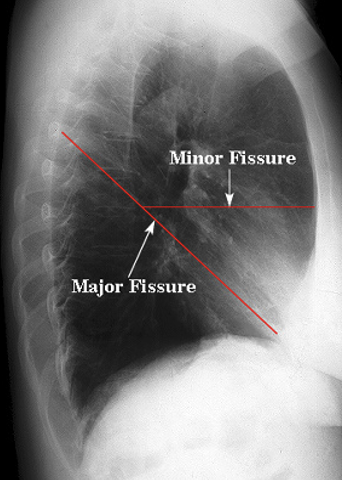

21

Which right lung fissure is oriented obliquely?

A

Major Fissure

22

The minor fissue separates which right lung lobes?

The RUL and RML